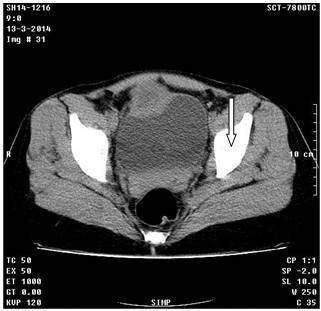

Continuaron las investigaciones con una tomografía axial computarizada de abdomen e hipogastrio, simple y contrastada, donde se observó ambos riñones normales, en fase nefográfica, sin litiasis y sin hidronefrosis, así como el parénquima conservado. Por encima de la vejiga y a la derecha de la línea media, se observó una imagen hipodensa de 38X41mm, con una pared gruesa de 12mm que aumentó su densidad con la administración de contraste, y con elemento metálico en su interior que impresionó ser un clip de ligadura, que al parecer pinzaba la cara anterior de la vejiga, todo ello relacionado con reacción inflamatoria y absceso a ese nivel. Además de la vejiga en repleción, se observó el útero de tamaño normal, anejos normales y densidades homogéneas. (Figuras 4 y 5). A la paciente se le realizó laparoscopia diagnóstica, con lo que se corroboró el diagnóstico. Se realizó cirugía para extracción del clip metálico. La evolución de la paciente fue satisfactoria.